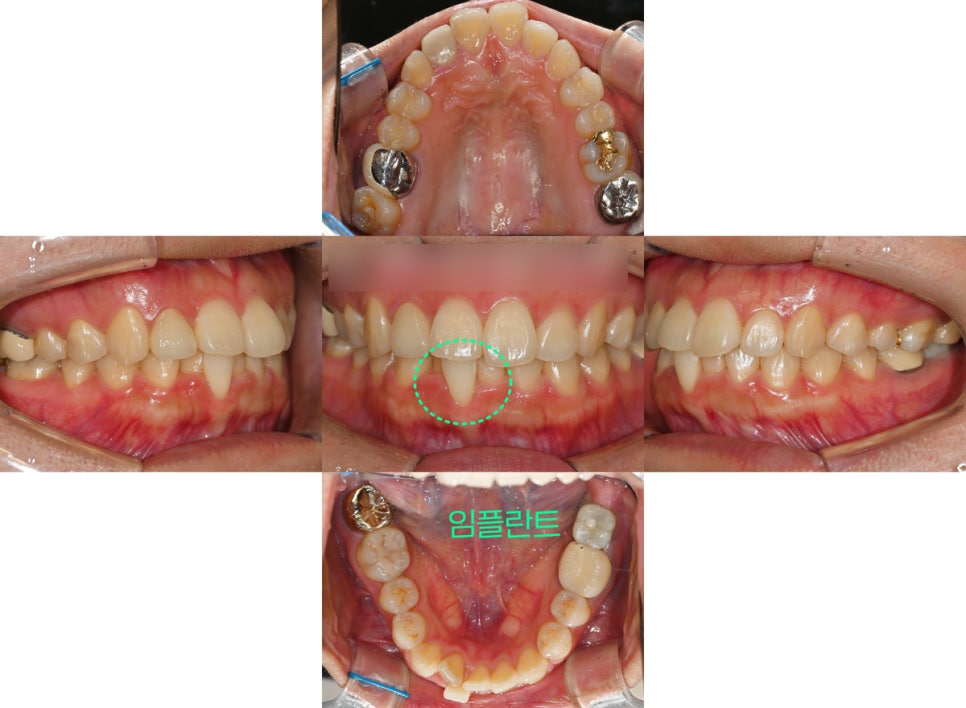

『1. 이가 삐뚤어요.』

이가 삐뚤다며 중화동 치과 에 오셨는데요.

초진 사진을 보면 위 앞니가

아래 앞니를 덮는 양이 과도합니다.

다행히 구치부 관계는 1급이였지만

왼쪽 아래 맨 뒤 어금니가 임플란트 치아였죠.

환자분의 제일 큰 고민은

고르지 않은 앞니였는데요.

골격적인 검진을 진행한 결과

다행히 정중선도 중앙에 잘 맞고 있는 편에 속했으며

돌출입 경향은 발견되지 않았습니다.

상악의 각도가 조금 과도하긴 하지만

크게 문제가 될 정도는 아니였죠^^